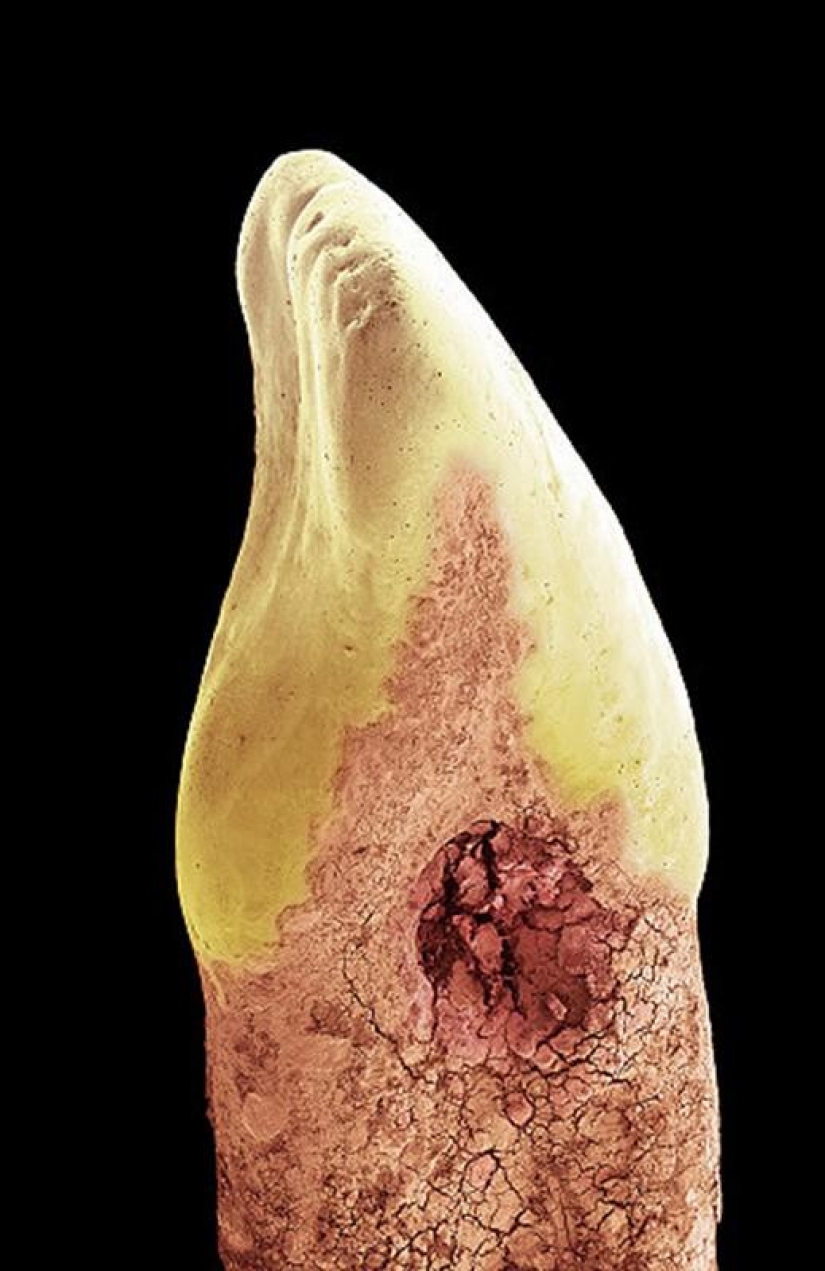

La leche en los dientes. Una gran parte de los humanos de los dientes de la dentina, una sustancia que envuelve a una cavidad en la que el suave tejido conectivo, vasos sanguíneos y nervios. A continuación, la corona del diente cubre el esmalte (la foto de arriba en blanco) — más fuerte y más mineralizada sustancia que protege la dentina de los ácidos en la boca. En la raíz del diente, la dentina está protegido por una sustancia llamada de cemento (rosa), que sirve como el medio por el cual los ligamentos periodontales pueden adherirse al diente para la estabilidad. (SPL / Barcroft Media)

Humanos incisivo con una cavidad o la pérdida de minerales causada por bacterias ácido "basura". En este caso, las cavidades formadas en el lado del diente (entre dos dientes) y de la encía (entre la corona — amarillo — y la raíz), tal vez debido a la falta de cepillado dental el hilo dental o de su uso inadecuado. Investigadores británicos encontraron que uno de cada tres adultos son propensos a la caries, y el estudio realizado en 5 años, los niños en 2012, mostró que cada 4-th de ellos tiene un diferente grado de caries. (SPL / Barcroft Media)

El diente de leche de la corona. Su raíz es estratificado como el resultado de un proceso conocido como temporal de la reabsorción de los dientes. Esto fue debido a la presión de la creciente de los dientes permanentes. (SPL / Barcroft Media)